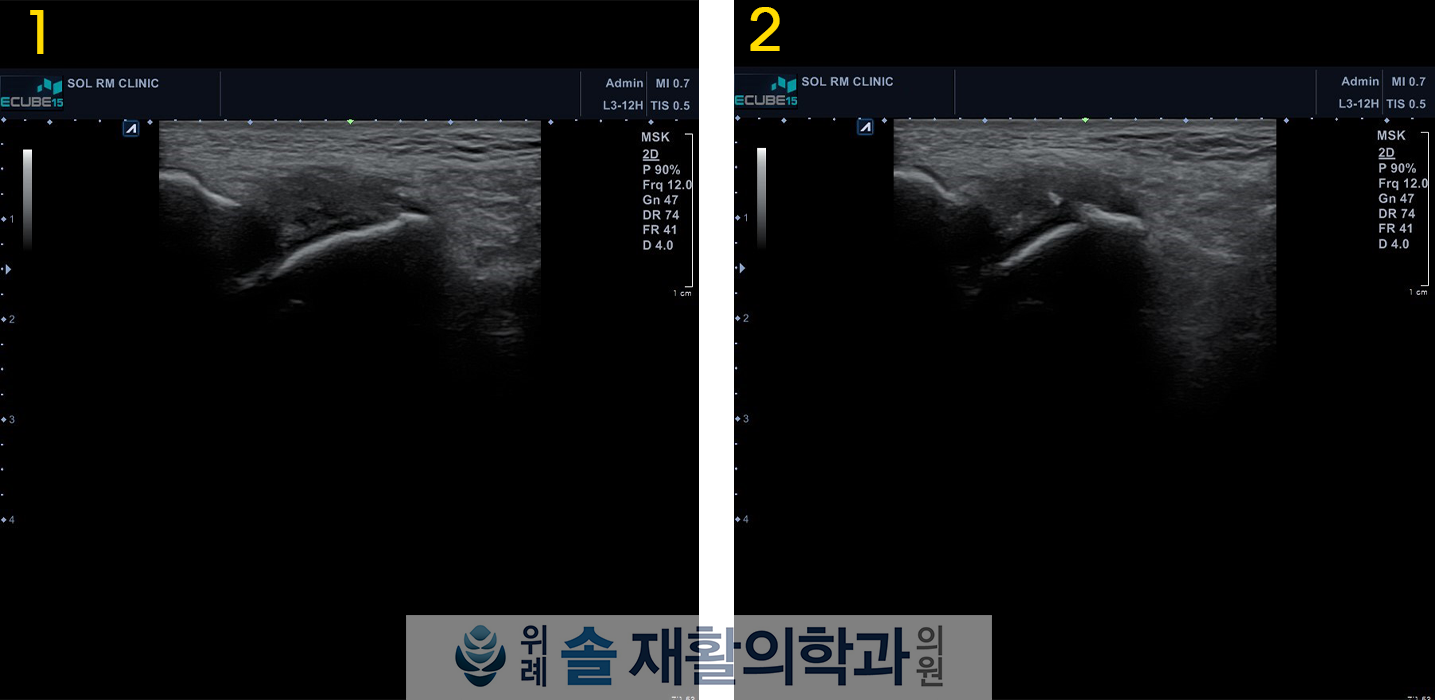

진찰 당시 멍은 다 빠져있었으나 약간의 붓기는 남아있었으며, 발목 외측 부위의 압통이 명확히 있었고, 반대측에 비해 발목이 약간 흔들리는 불안정성을 보이고 있었습니다. 발목 엑스레이 검사와 초음파 검사를 바로 시행했응며, 발목 외측 인대 중 2개의 파열 소견이 관찰되었습니다. 파열된 인대는 가장 흔하게 손상되는 1,2위 인대로 전거비인대(Anterior talofibular ligament)와 종비인대(Calcaneofibular ligament)의 거의 전층 파열이 확인되었습니다.

CASE의 환자는 이미 2주가 지나서 불안정성이 확인된 상태로 왔기 때문에, 내원 시점에서 반깁스 고정까지는 필요하지 않았고 손상된 인대를 회복시키는 것이 급선무여서, 조직재생주사(DNA주사)치료와  체외충격파치료를 통하여 인대의 재생을 유도하고 발목 보조기를 착용하여 발목에 무리가 가지 않도록 보호하였습니다.

주사치료와 체외충격파치료를 각각 3회씩 시행하였으며, 이 후 통증은 많이 가라앉아 6주 후 초음파검사를 재시행 해보았더니, 기존의 발목 인대 파열 부위에  새살이 돋아 매꿔져있음을 확인할 수 있었습니다.